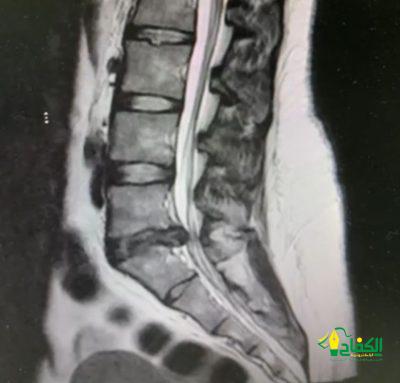

وبعد إجراء الفحوصات اللازمة، تبيّن وجود انزلاق غضروفي بين الفقرة القَطنية الخامسة والعَجُزية الأولى وقرر الفريق الطبي إجراء عملية جراحية بعد أن فشلت المسكنات والعلاج الطبيعي في النتائج المرجوة في تخفيف الألم، وبعد تنويم المريضة أُجريت لها عملية إزالة الغضروف الضاغط على الأعصاب باستخدام تقنية التدخل المحدود بالمنظار، عبر فتحة جراحية صغيرة لا تتجاوز 2 سم، وخرجت المريضة من المستشفى بعد يوم واحد من العملية وهي في حالة صحية جيدة.

وأوضح استشاري جراحة العمود الفقري الدكتور سلطان بن عتيق الفايدي أن “استخدام تقنية المنظار في هذه العمليات يُعتبر خيارًا فعالًا لتخفيف الآلام وتحسين حياة المرضى بشكل سريع وآمن.